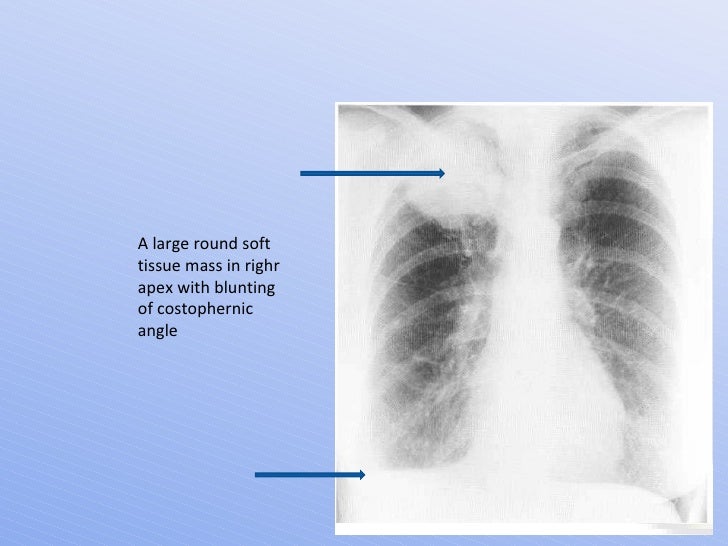

X-Ray Chest: Carcinoma Lung

lung carcinoma xray tissue